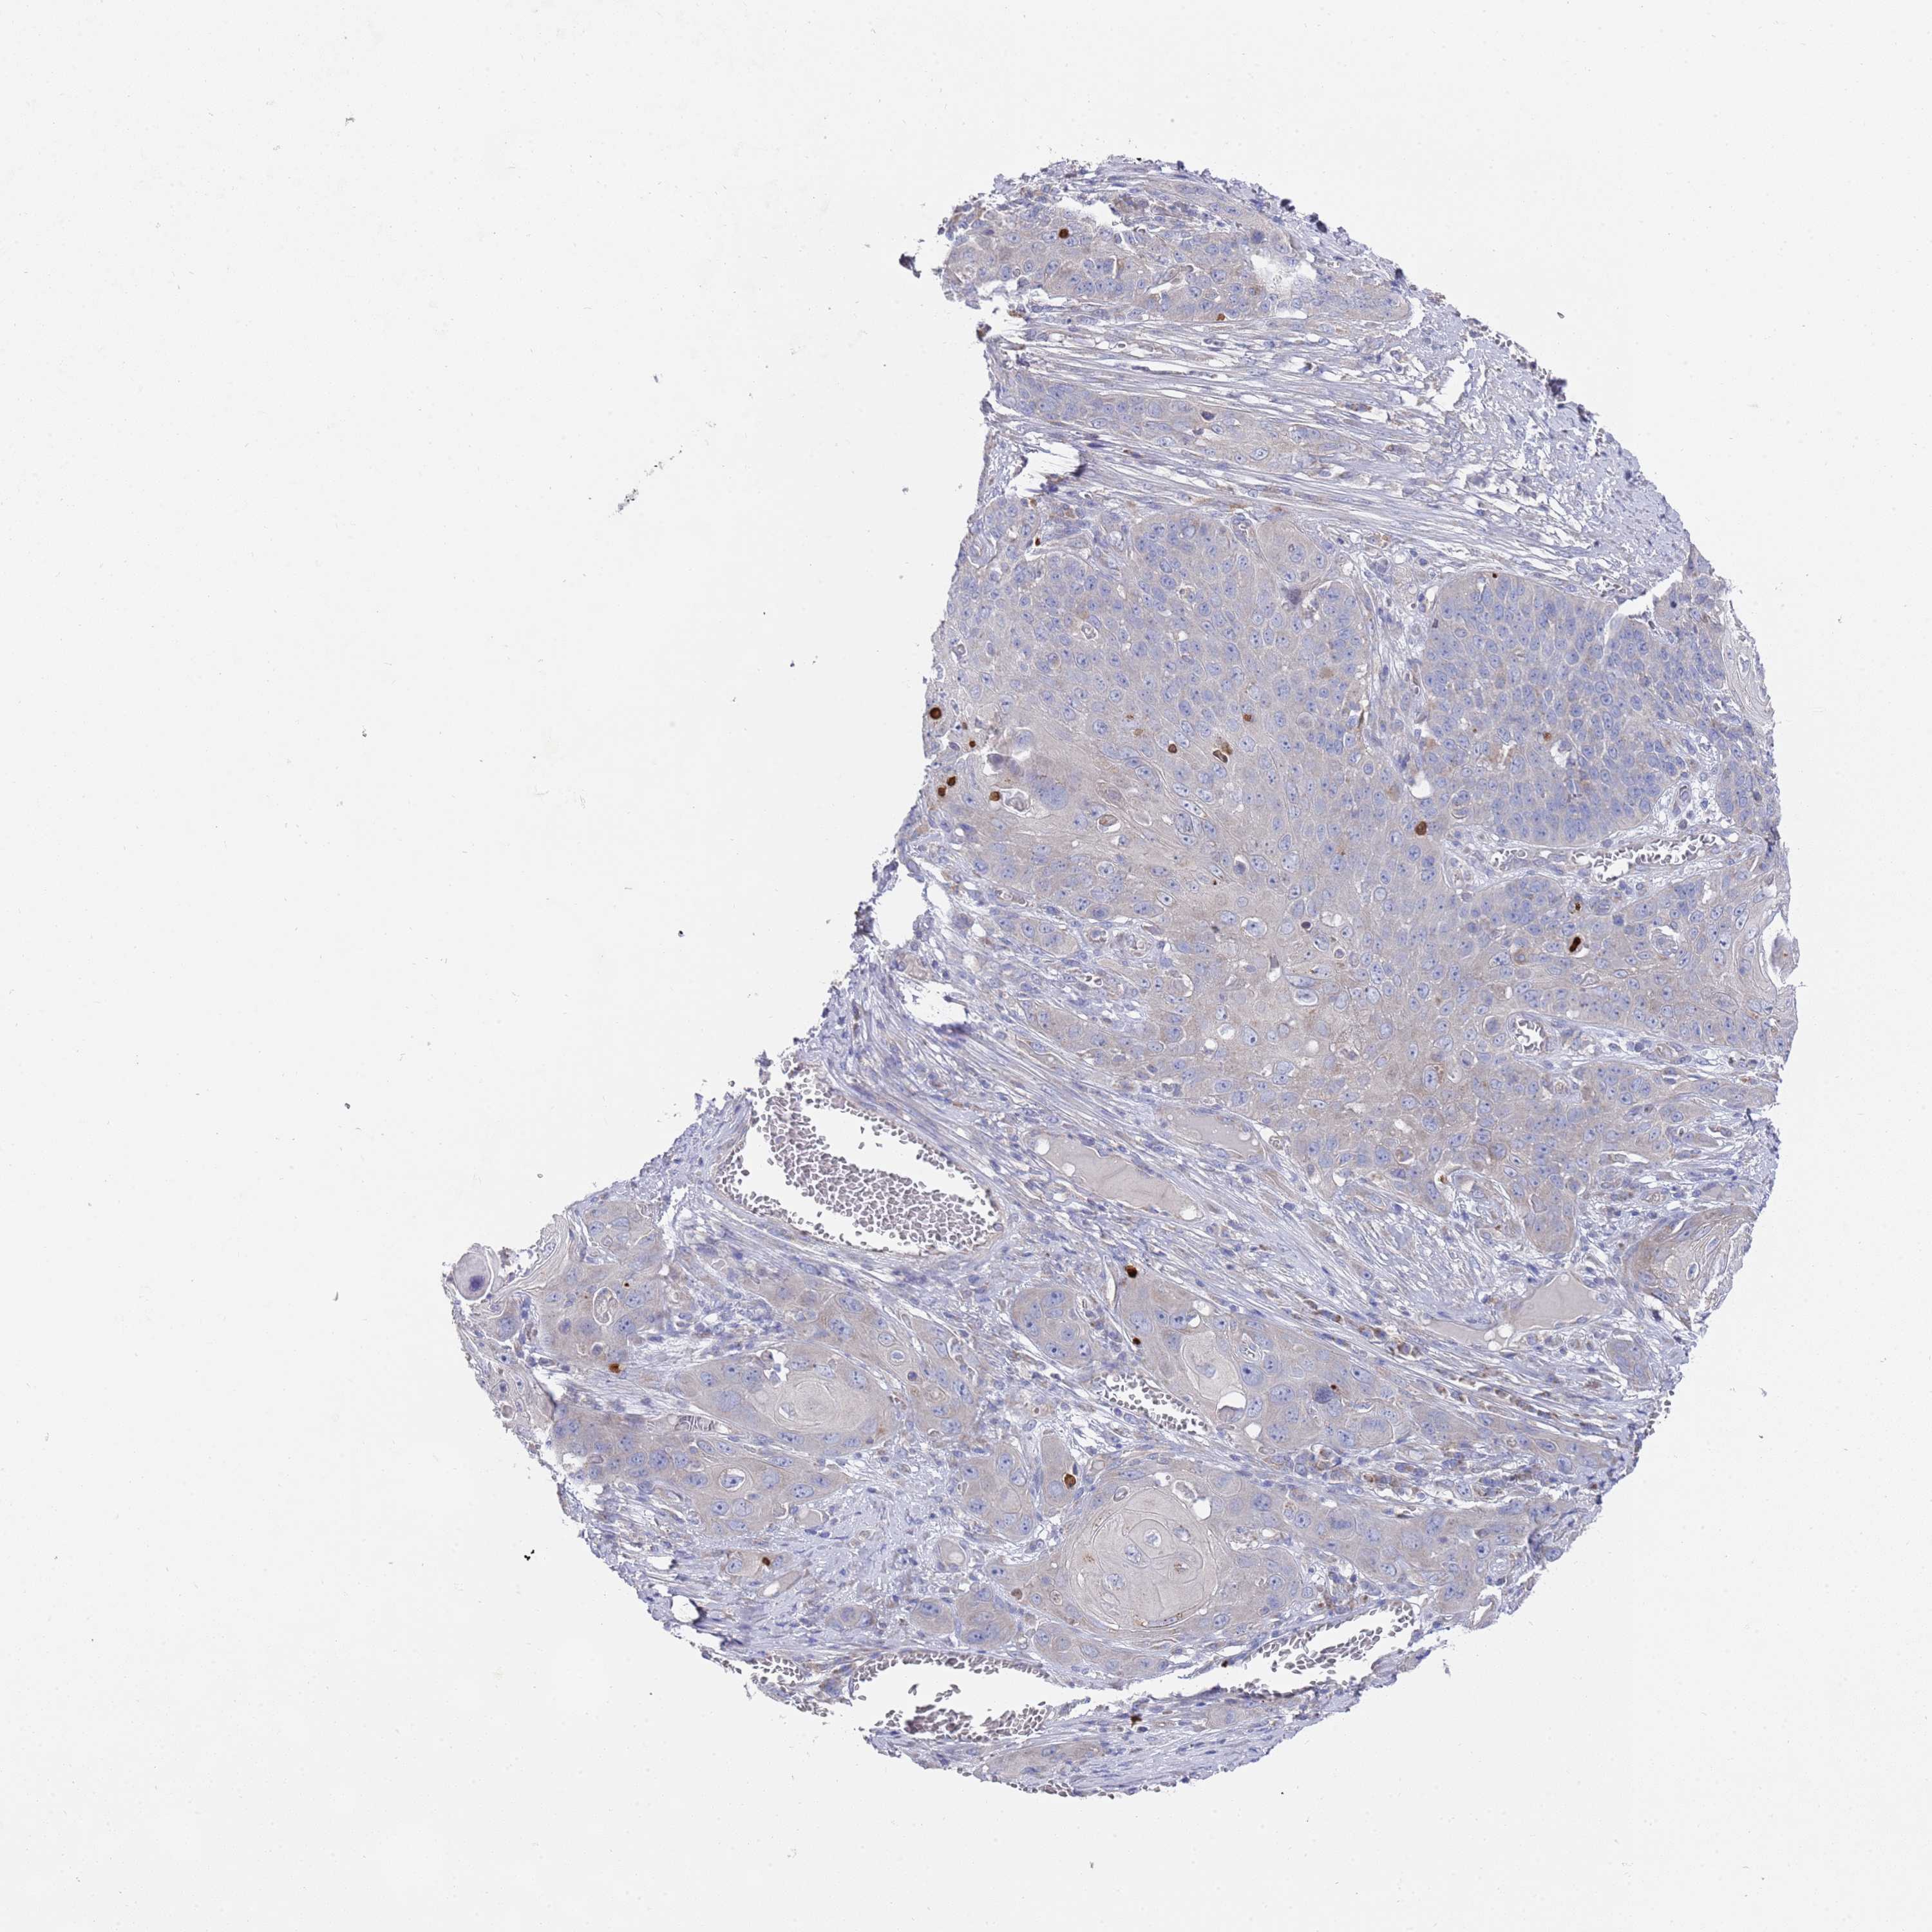

SKIN CANCER - Protein expressioni

A mouse-over function shows sample information and annotation data. Click on an image to view it in a full screen mode. Samples can be filtered based on level of antibody staining by selecting one or several of the following categories: high, medium, low and not detected. The assay and annotation is described here.

Each image is clickable and will lead to virtual microscopy that enables deeper exploration of all samples and also displays staining intensity scores, fraction scores and subcellular localization as well as patient and tissue information for each sample.

Antibody HPA021453

Staining

Not detected

Negative

None

Squamous cell carcinoma, NOS